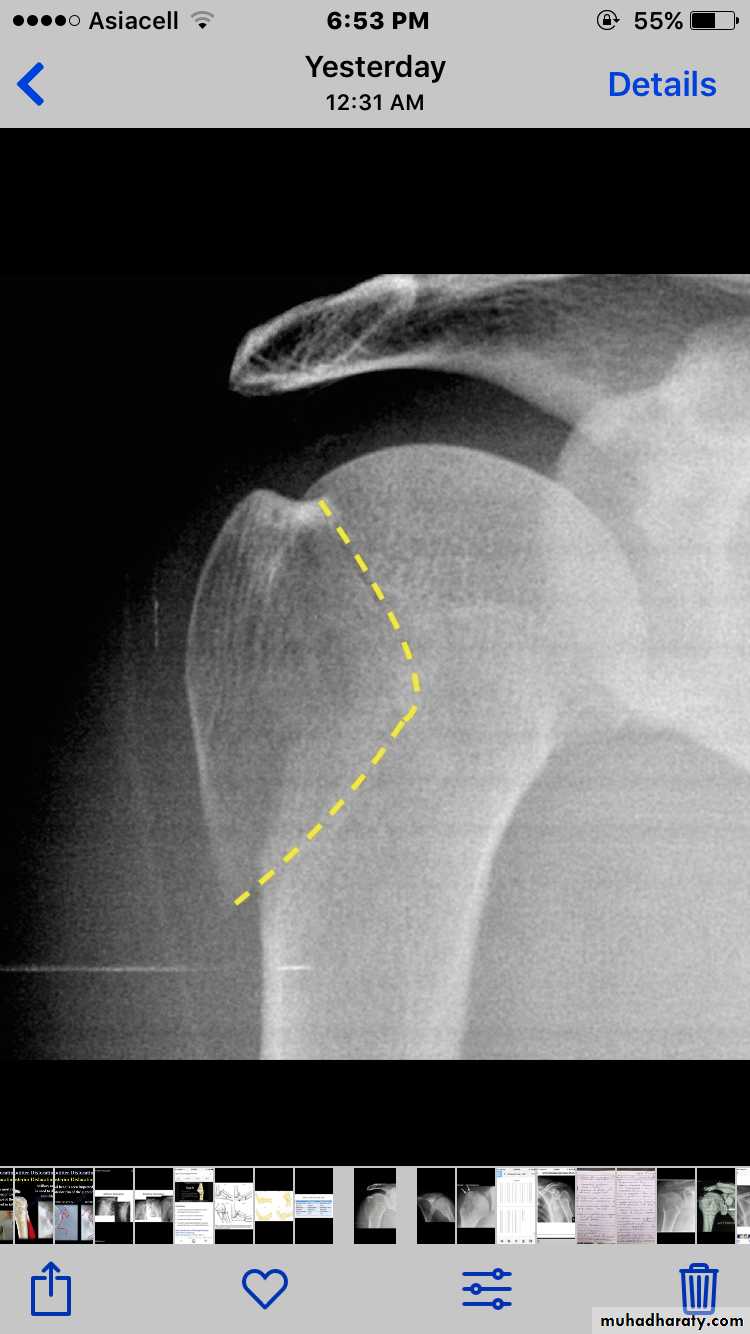

X RAY